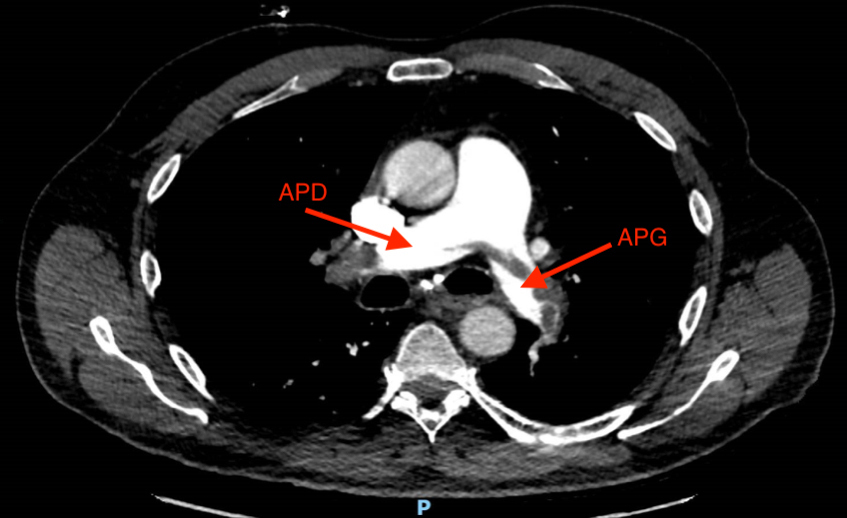

L’échographie cardiaque donnera le diagnostic.

– la tamponnade liquidienne (l’échographie cardiaque donnera le diagnostic) ;

– l’embolie pulmonaire grave (l’échographie cardiaque affinera le diagnostic en cas de dilatation des cavités droites.